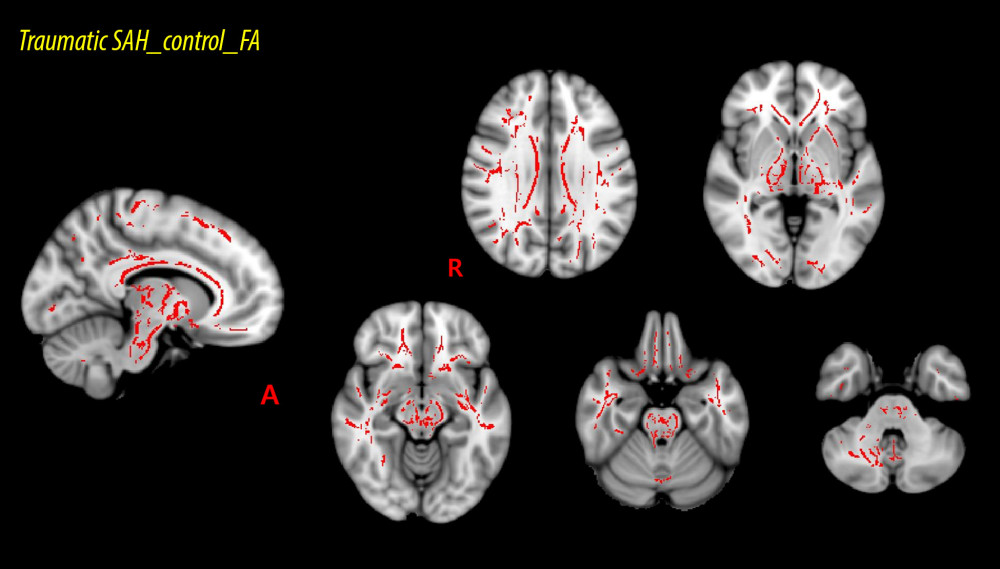

MATERIAL AND METHODS: For this study, 10 isolated traumatic subarachnoid hemorrhage patients and 10 age- and sex-matched healthy control subjects were recruited. Fractional anisotropy data voxel-wise statistical analyses were conducted through the tract-based spatial statistics as implemented in the FMRIB Software Library. Depending on the intersection between the fractional anisotropy skeleton and the probabilistic white matter atlases of Johns Hopkins University, we calculated mean fractional anisotropy values within the entire tract skeleton and 48 regions of interest.

RESULTS: The fractional anisotropy values for 19 of 48 regions of interest showed significant divergences (P<0.05) between the patient group and control group. The regions showing significant differences included the corpus callosum and its adjacent neural structures, the brainstem and its adjacent neural structures, and the subcortical white matter that passes the long neural tract.

All data analyses were conducted utilizing the functional MRI evaluation tool through the FMRIB software library (FSL) [38]. Fractional anisotropy (FA) maps were created using a previously described method [27]. Using TBSS realized in the FSL, voxel-wise statistical analysis of the FA data was conducted [39]. To sort the FA data for all subjects into a common space, a nonlinear registration algorithm (www.doc.ic.ac.uk/~dr/software) was utilized [38]. A mean FA image was generated and then thinned to make a mean FA skeleton showing the centroids of all areas common to the group subjects [38]. We then applied a threshold to and binarized the mean FA skeleton at an FA level >0.2, and the adjusted data were entered into the voxel-wise statistics process. Then, for each subject, the sorted FA data were reflected to the mean skeleton, and to assess the FA values’ differences between each group, voxel-wise cross-subject statistics were acquired [38]. The results were adjusted to control the family-wise error rate to allow multiple comparisons after conducting threshold-free cluster enhancement [38]. To confirm the mean FA values of each subject and observe the differences for each tract, voxels recognized as TBSS were chosen. We assessed mean FA values within the skeleton and 48 regions of interest (ROIs) that were depending on crossing between the entire skeleton and the probabilistic white matter atlases of Johns Hopkins University for organizing the FA data in each of the white matter regions [38]. Differences in the FA values among the 48 ROIs were determined by subtracting the average FA value of the patient group from that of the control group. The obtained FA values’ differences were then arranged in descending order.

The voxel-wise FA values’ differences between the patient and control groups are listed in Table 2 and, all of the ROIs are presented in ascending order, beginning with the ROI with the lowest

The current study investigated microstructural differences in the subcortical white matter of the patient and control groups and obtained the following results: 1) FA values of the patient group were lower than those of the control group in 19 of the 48 white matter ROIs; 2) the ROIs with the lowest ratios for the FA values between the patient and control groups were associated with the corpus callosum and its adjacent neural structures (the corpus callosum and the cingulum), the brainstem and its adjacent neural structures (the cerebral peduncle, the superior and middle cerebellar peduncle), the subcortical white matter that passes the long neural tracts (the internal capsule, the corona radiata, the corticospinal tract, the external capsule, and the superior longitudinal fasciculus).